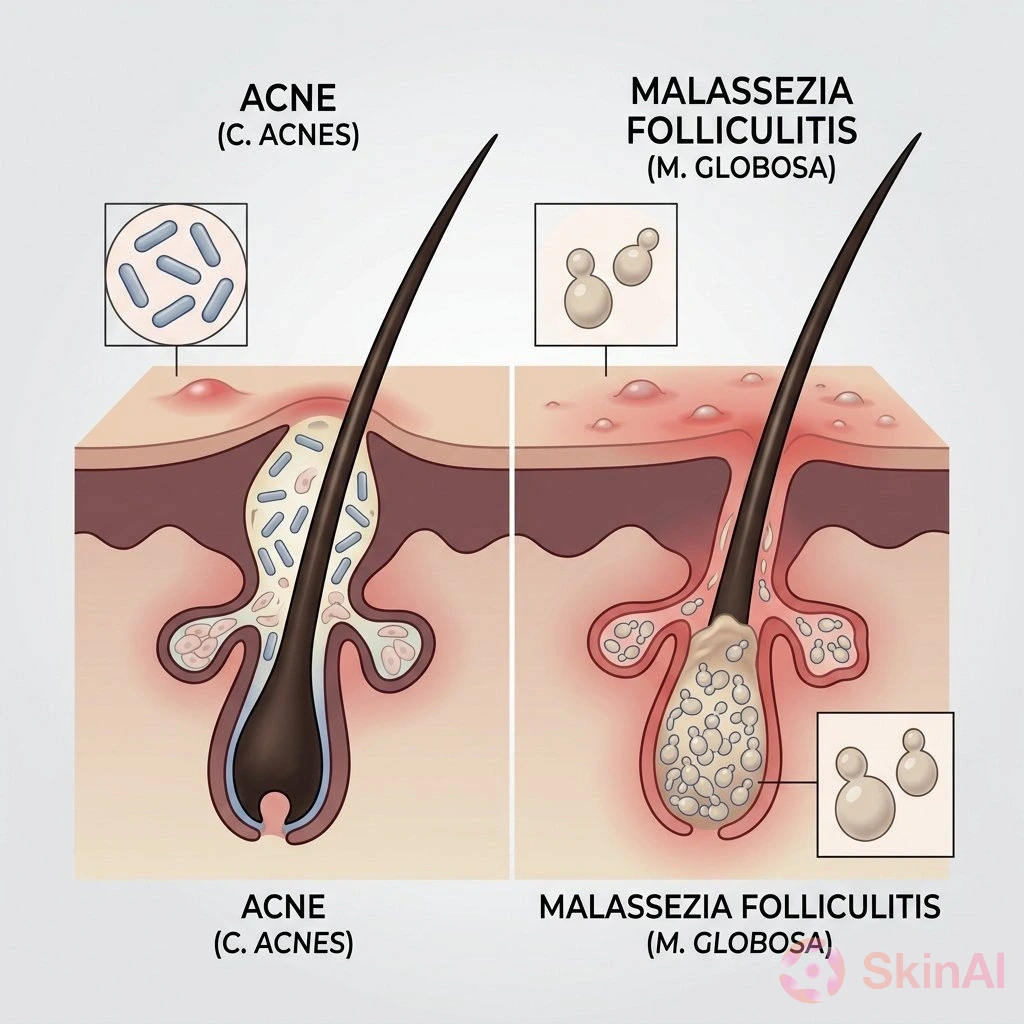

Malassezia Folliculitis vs Acne: How to Spot and Treat the Difference

Discover how to tell Malassezia folliculitis from acne and learn the best treatments for each to clear your skin effectively...